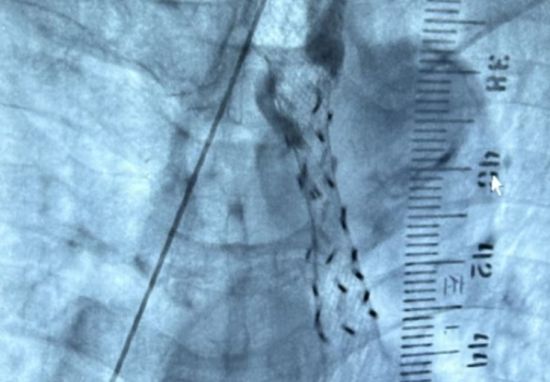

“这就是食道粒子支架植入术,是一种将有放射性125碘支架植入到食管腔中治疗食道癌的治疗技术。”叶斌说,普通支架只是机械扩张,但不能抑制癌细胞的生长,而放射性粒子支架,不但可以起到机械扩张的作用,同时能够通过放射线作用达到近距离放疗的作用,杀灭肿瘤细胞,从而实现食道癌的标本兼治目的,是食道癌患者延长生命的良好保障手段。

最终,在成都市第六人民医院肿瘤科、介入医学科、放射影像科等多学科协作下,顺利为侯大爷完成了食道粒子支架植入术,使其因食管癌导致的食道梗阻恢复通畅。食道粒子支架植入术具有针对性强、伤害小、疗效明显、并发症少及成本效益比高等优点。术后第二天,候大爷即可进流质饮食,营养状况和精神状态也较术前明显改善,患者及家属对术后效果十分满意。